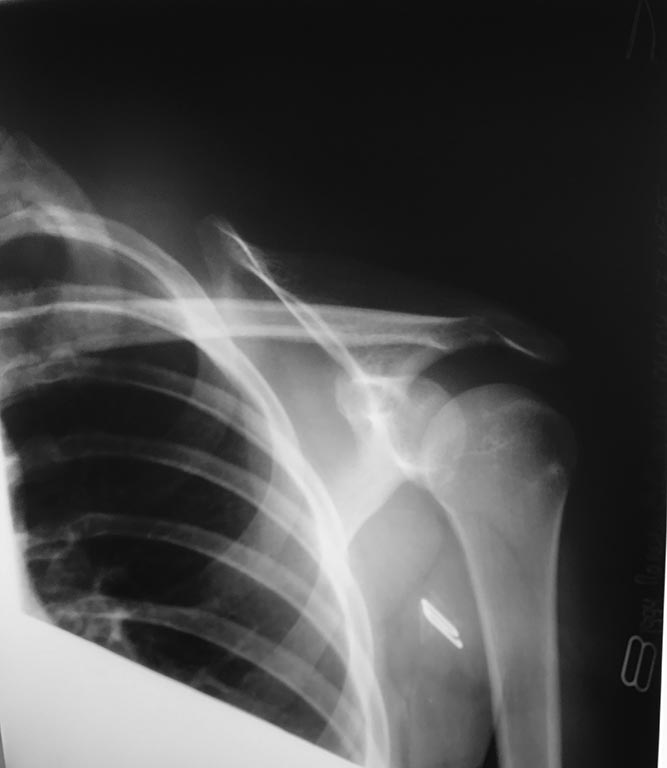

Многоуважаемые коллеги помогите советом. Обратилась девочка 15 лет с болями в левом плечевом суставе,упала на лопатку.

При клиническом осмотре определяется асимметрия в положении лопаток(левая лопатка располагается латеральнее и немного дорсальнее(более выпуклая) в сравнении с правой),которая устраняется при сведении лопаток. Из анамнеза известно, что первый аналогичный случай был после удара дверью по лопатке. Тогда,со слов, в травматологическом отделении под общим обезболиванием восстанавливался полный объём движений(непосредственно вывиха плеча не было).А далее было несколько аналогичных случаев, но лечение проводилось без хирургической тактики. Проходили обследование в других клиниках, но толкового ответа нигде не услышали. Делали мрт плечевого сустава, патологии не выявлено. Можно ли установить диагноз привычный подвывих лопатки вследствие частичного повреждения мышц плечевого пояса. Нестабильность левой лопатки?Какова тактика действий,встречались ли вы с такими случаями?

Добрый день. Учитывая травму рассматривали ли Вы вариант повреждения длинного грудного нерва? Дообследовать - ЭНМГ и проверить "wall press up test".

Добрый день! А что за история с вправлением под общим обезболиванием, выписки, снимки есть? Если по МРТ - без патологии, то о поражении каких мышц области плечевого сустава идёт речь? Вопрос банальный, но тем не менее, а что с позвоночником вообще? Я бы подумал об экзостозе внутренней поверхности лопатки или прилегающих участков рёбер. Лопатка не та кость, для которой типичны подвывихи, учитывая её мышечное покрытие.

Действительно, похоже на нейропатию длинного грудного нерва и,как следствие, синдром крыловидный лопатки. Целесообразна ЭМГ сравнительная зубчатых мышц, определение объема активных движений строго в плечевом суставе, положения лопатки при активных боковом и переднем отведениях, поднятии верхней конечности.